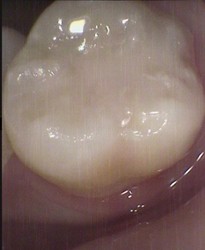

Before ~ mild decay permanent molar After ~ small white filling